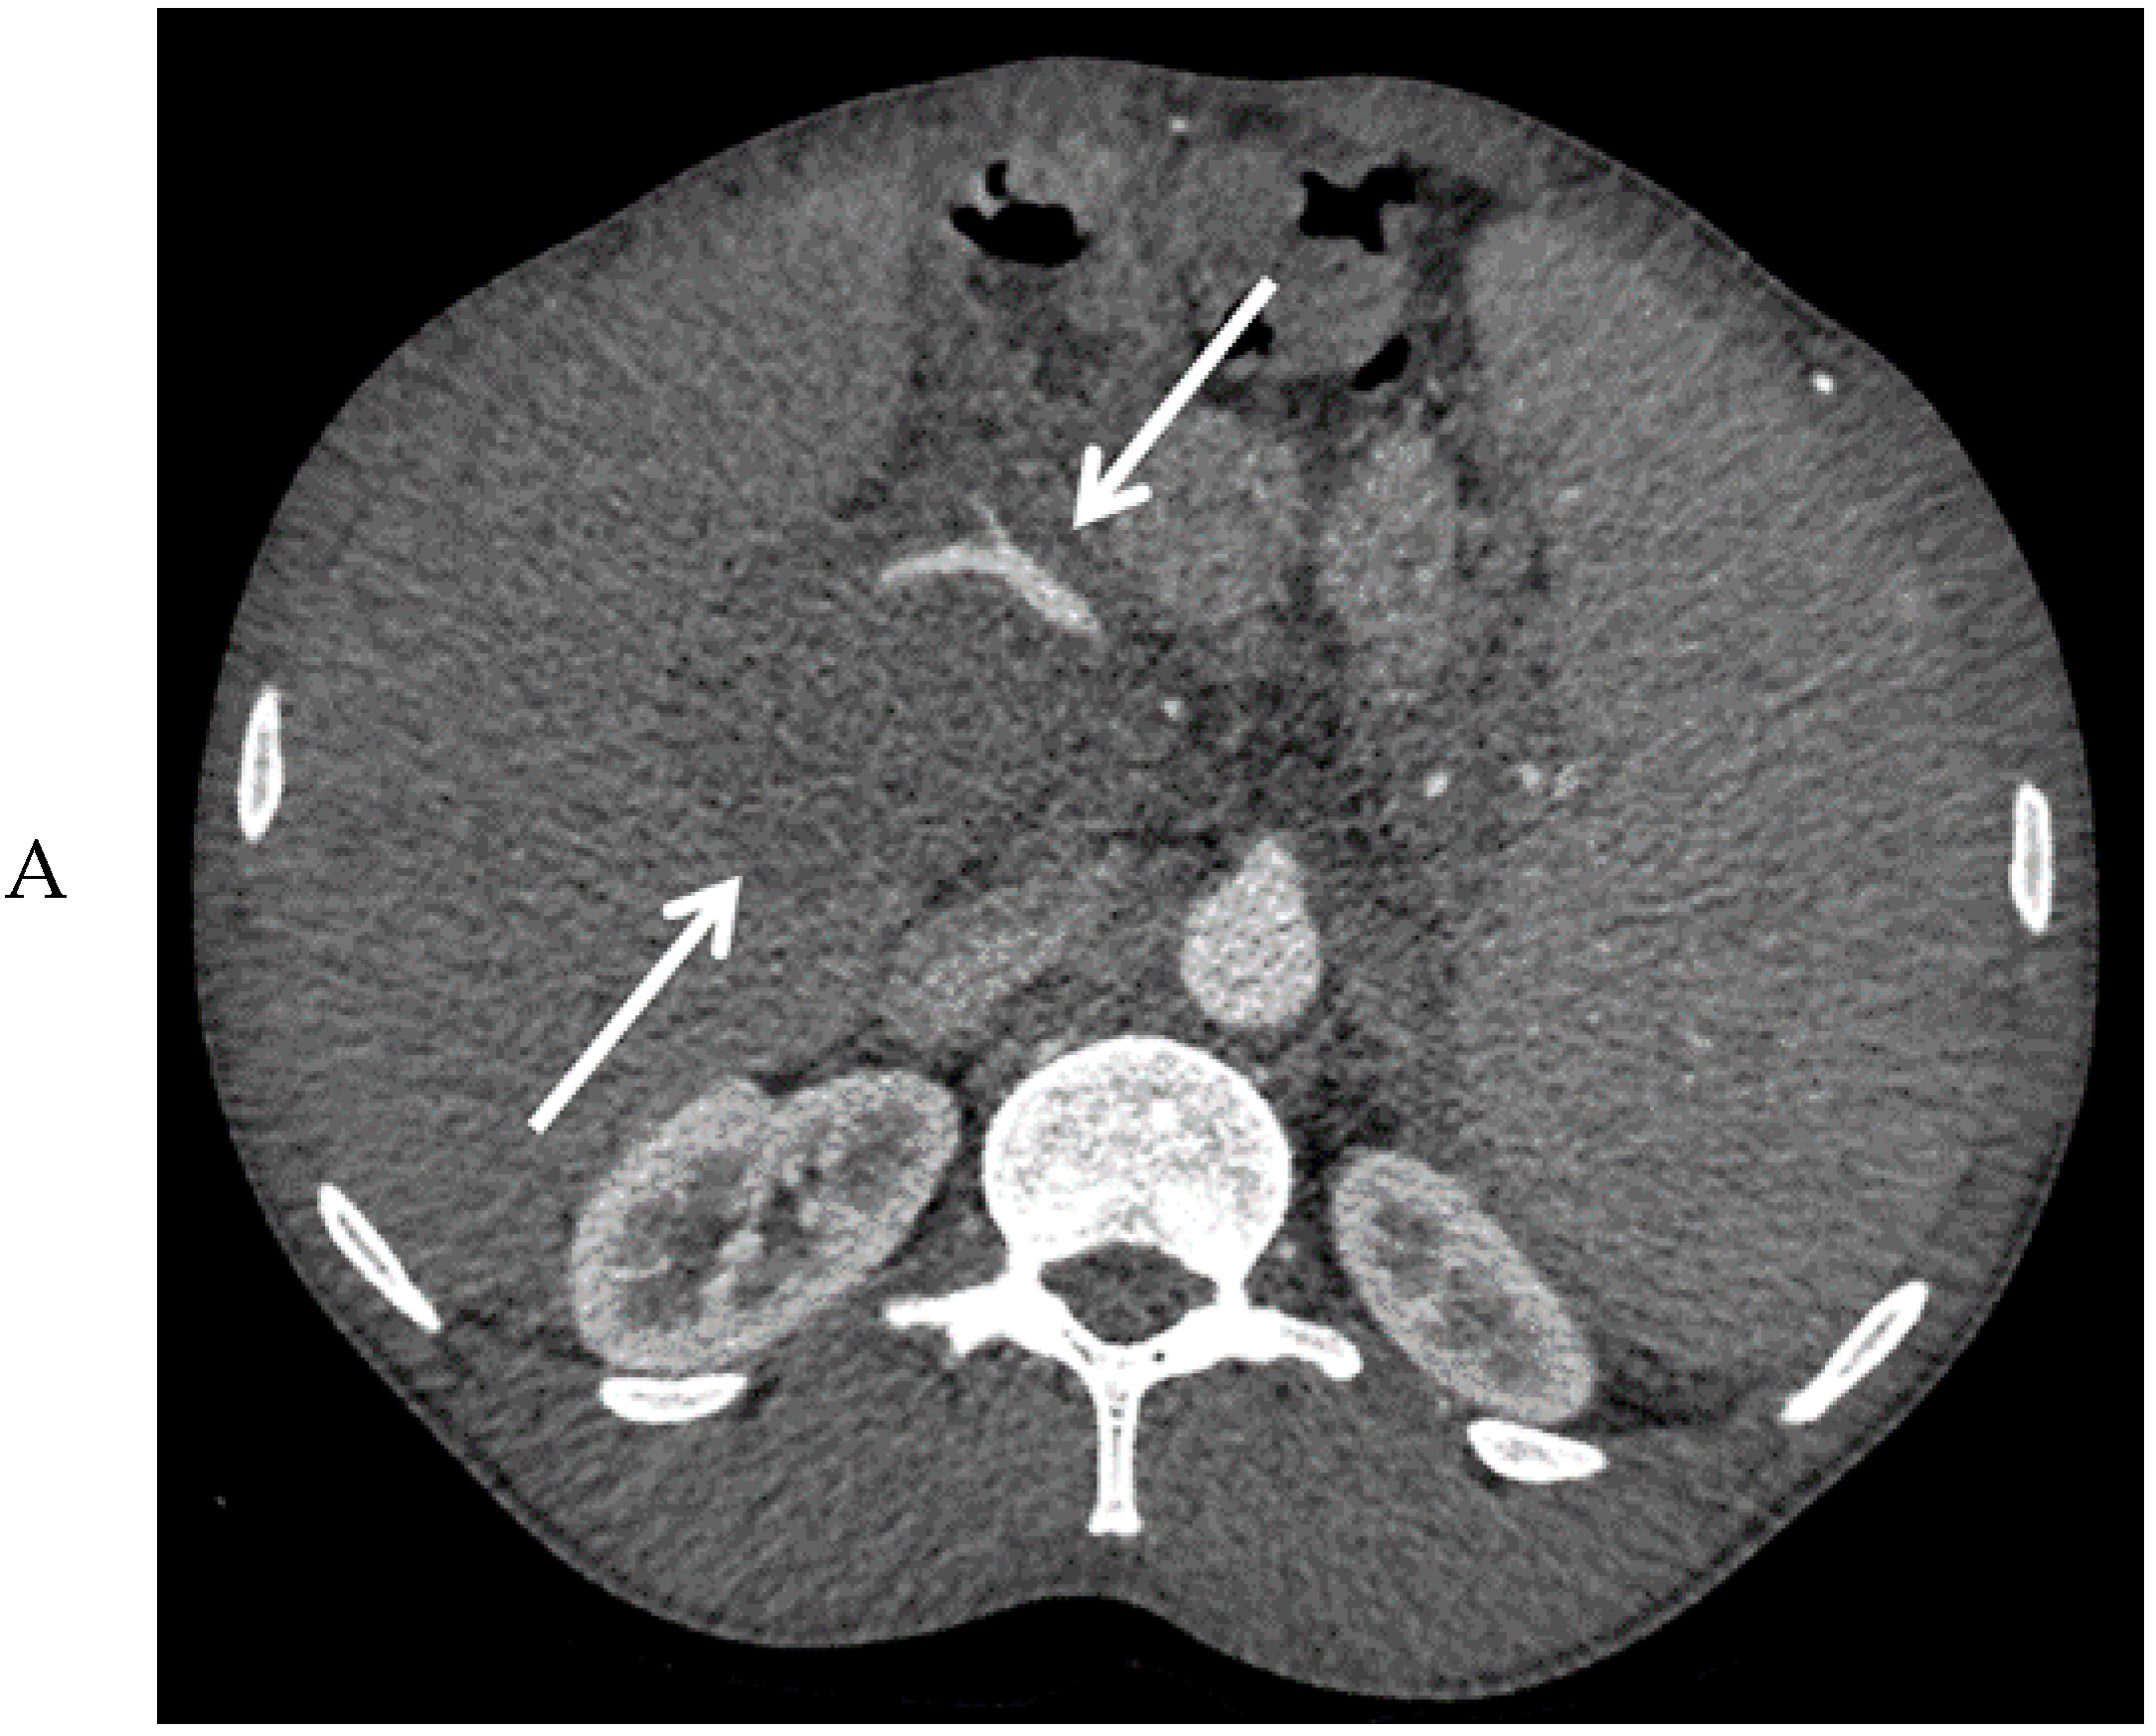

Figure 2.

Computed tomography images of the mass in the upper abdomen (arrows) in the arterial (A) and portal venous phase (B).